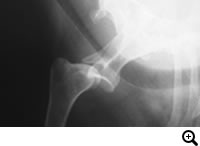

肩関節脱臼

症状:飛び降りた拍子、高所から落下した拍子、もしくは普通の生活の中で起こった突然の前足の挙上

肩関節脱臼とは

肩関節が外れた状態、内方脱臼と外方脱臼があります。

診断

レントゲン検査

治療

手術をせずに整復し固定をおこなっても治ることが少なく、外科的に脱臼を整復し固定する必要がある場合が多いです。内方脱臼ではスーチャーアンカーを用いて整復する方法など、外方脱臼では二頭筋腱の転移術などを行います。それでも再脱臼する場合、最終的な救済処置として関節固定術を行うこともあります。